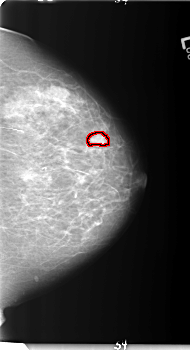

B_3152_1.LEFT_MLO

LEFT_MLO LINES 5992 PIXELS_PER_LINE 3480 BITS_PER_PIXEL 12 RESOLUTION 50 OVERLAY

FILE: B_3152_1.LEFT_MLO.OVERLAY

TOTAL_ABNORMALITIES 1

ABNORMALITY 1

LESION_TYPE MASS SHAPE LOBULATED MARGINS CIRCUMSCRIBED

ASSESSMENT 4

SUBTLETY 4

PATHOLOGY BENIGN

TOTAL_OUTLINES 1

BOUNDARY